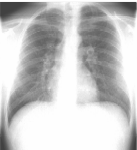

Συγκρίνετε το αποτέλεσμα ρύθμισης φωτεινότητας και ρύθμισης φωτεινότητας πολλαπλών κλιμάκων σε μια εικόνα θώρακα CR:

Μια εικόνα με αυξημένη αντίθεση που χρησιμοποιεί ρύθμιση φωτεινότητας εμφανίζει αποκοπή

Συνήθης ρύθμιση φωτεινότητας